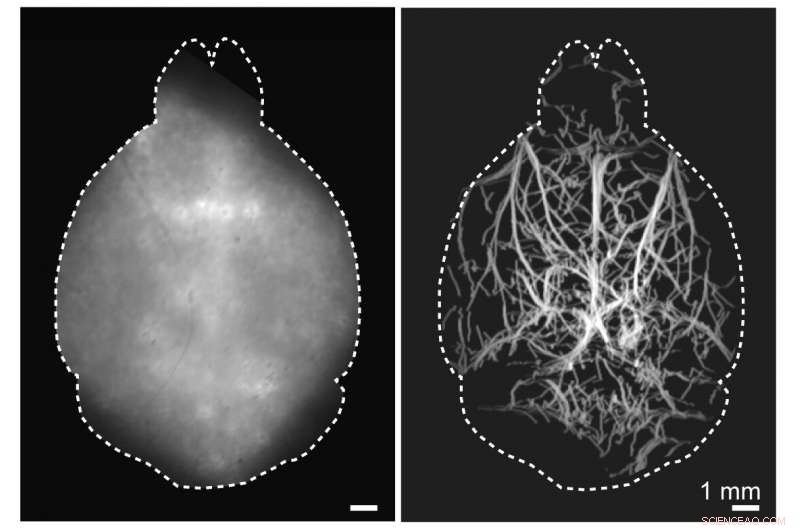

A new imaging method can capture images of vasculature deep in the brains of mice. A conventional widefield fluorescence image of the mouse brain taken non-invasively in the visible light spectrum is shown on the left, while the non-invasive localization-based DOLI approach operating in the NIR-II spectral window is shown on the right. Credit: Daniel Razansky, University and ETH Zurich

Researchers have developed a new technique that allows microscopic fluorescence imaging at four times the depth limit imposed by light diffusion. Fluorescence microscopy is often used to image molecular and cellular details of the brain in animal models of various diseases but, until now, has been limited to small volumes and highly invasive procedures due to intense light scattering by the skin and skull.

In Optica, the researchers describe their new technique, which is called diffuse optical localization imaging (DOLI). It takes advantage of what is known as the second near-infrared (NIR-II) spectral window from 1000 to 1700 nanometers, which exhibits less scattering.

The researchers first tested the new technique in synthetic models of tissue known as tissue phantoms that mimic average brain tissue properties, demonstrating that they could acquire microscopic resolution images at depths of up to 4 millimeters in optically opaque tissues. They then performed DOLI in living mice where cerebral microvasculature as well as blood flow velocity and direction could be visualized entirely noninvasively.